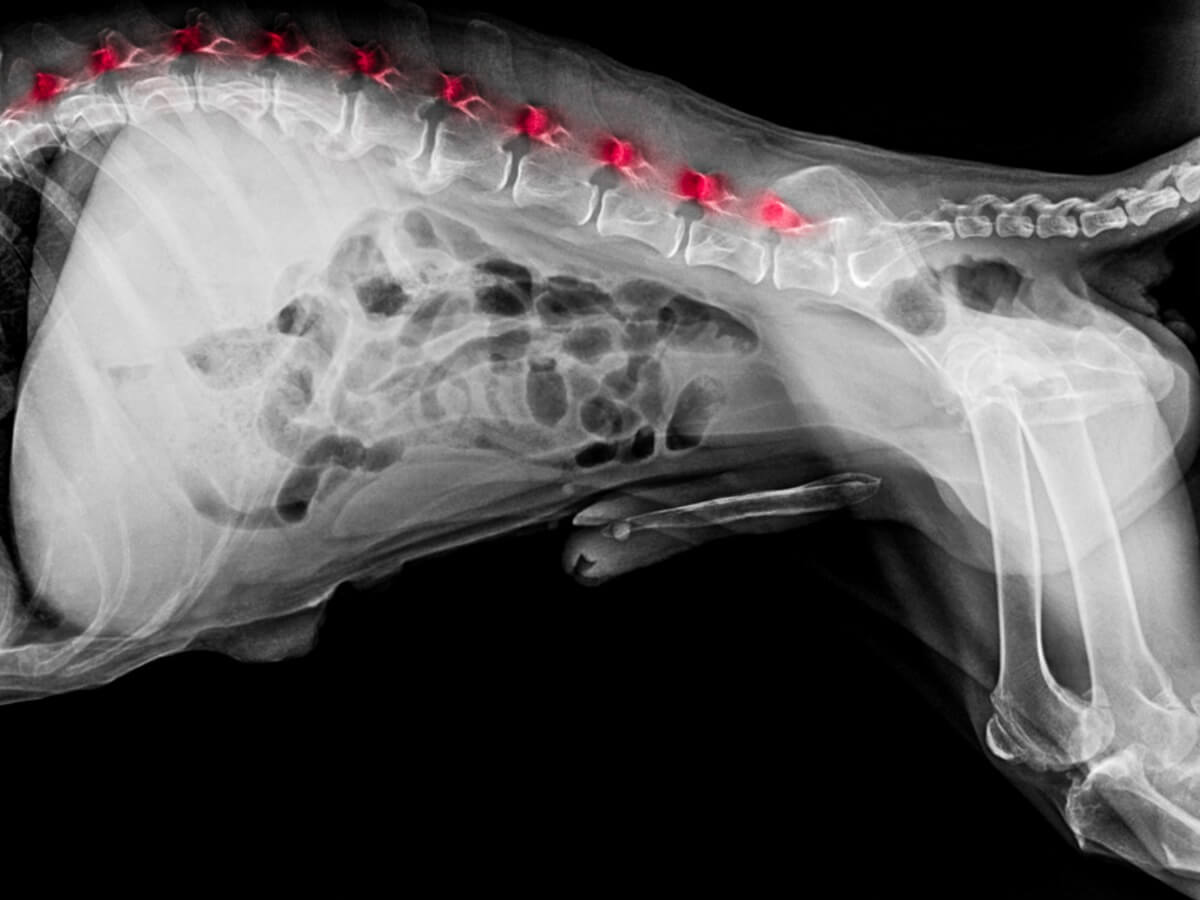

Zuerst einmal überprüft der Tierarzt die Reflexe und Verhaltensweisen des Hundes angesichts verschiedener Reize. Wenn er etwas Verdächtiges bemerkt, ordnet er in der Regel eine Röntgenuntersuchung oder MRT an. Darüber hinaus kann auch ein Blutbild zur Diagnosestellung erforderlich sein.